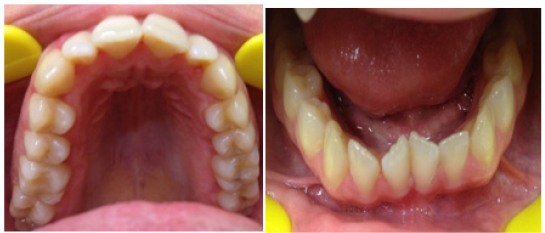

Figure 1B Pre-treatment intra-oral occlusal view photographs.

The patient is a 24-year-old female who presented to the second author’s private practice in Athens, Greece with a chief complaint of esthetic concerns with her smile and with difficulty chewing (Figure 1). On examination the patient has a mesoproscopic facial form, with an open bite of 5 mm, measured from maxillary and mandibular incisal edges and an overjet of 4mm. The maxillary arch is relatively narrow when compared to the mandible with a molar transverse discrepancy of 3mm. Functionally, the patient only occludes on her second premolars and molars while in maximum intercuspation. Although this patient did not exhibit sleep apnea symptoms, it is often associated with patients having a similar clinical presentation which may develop because of a constricted airway.4,5 Examination of the oral soft tissue, periodontium and dentition revealed slight marginal edema.